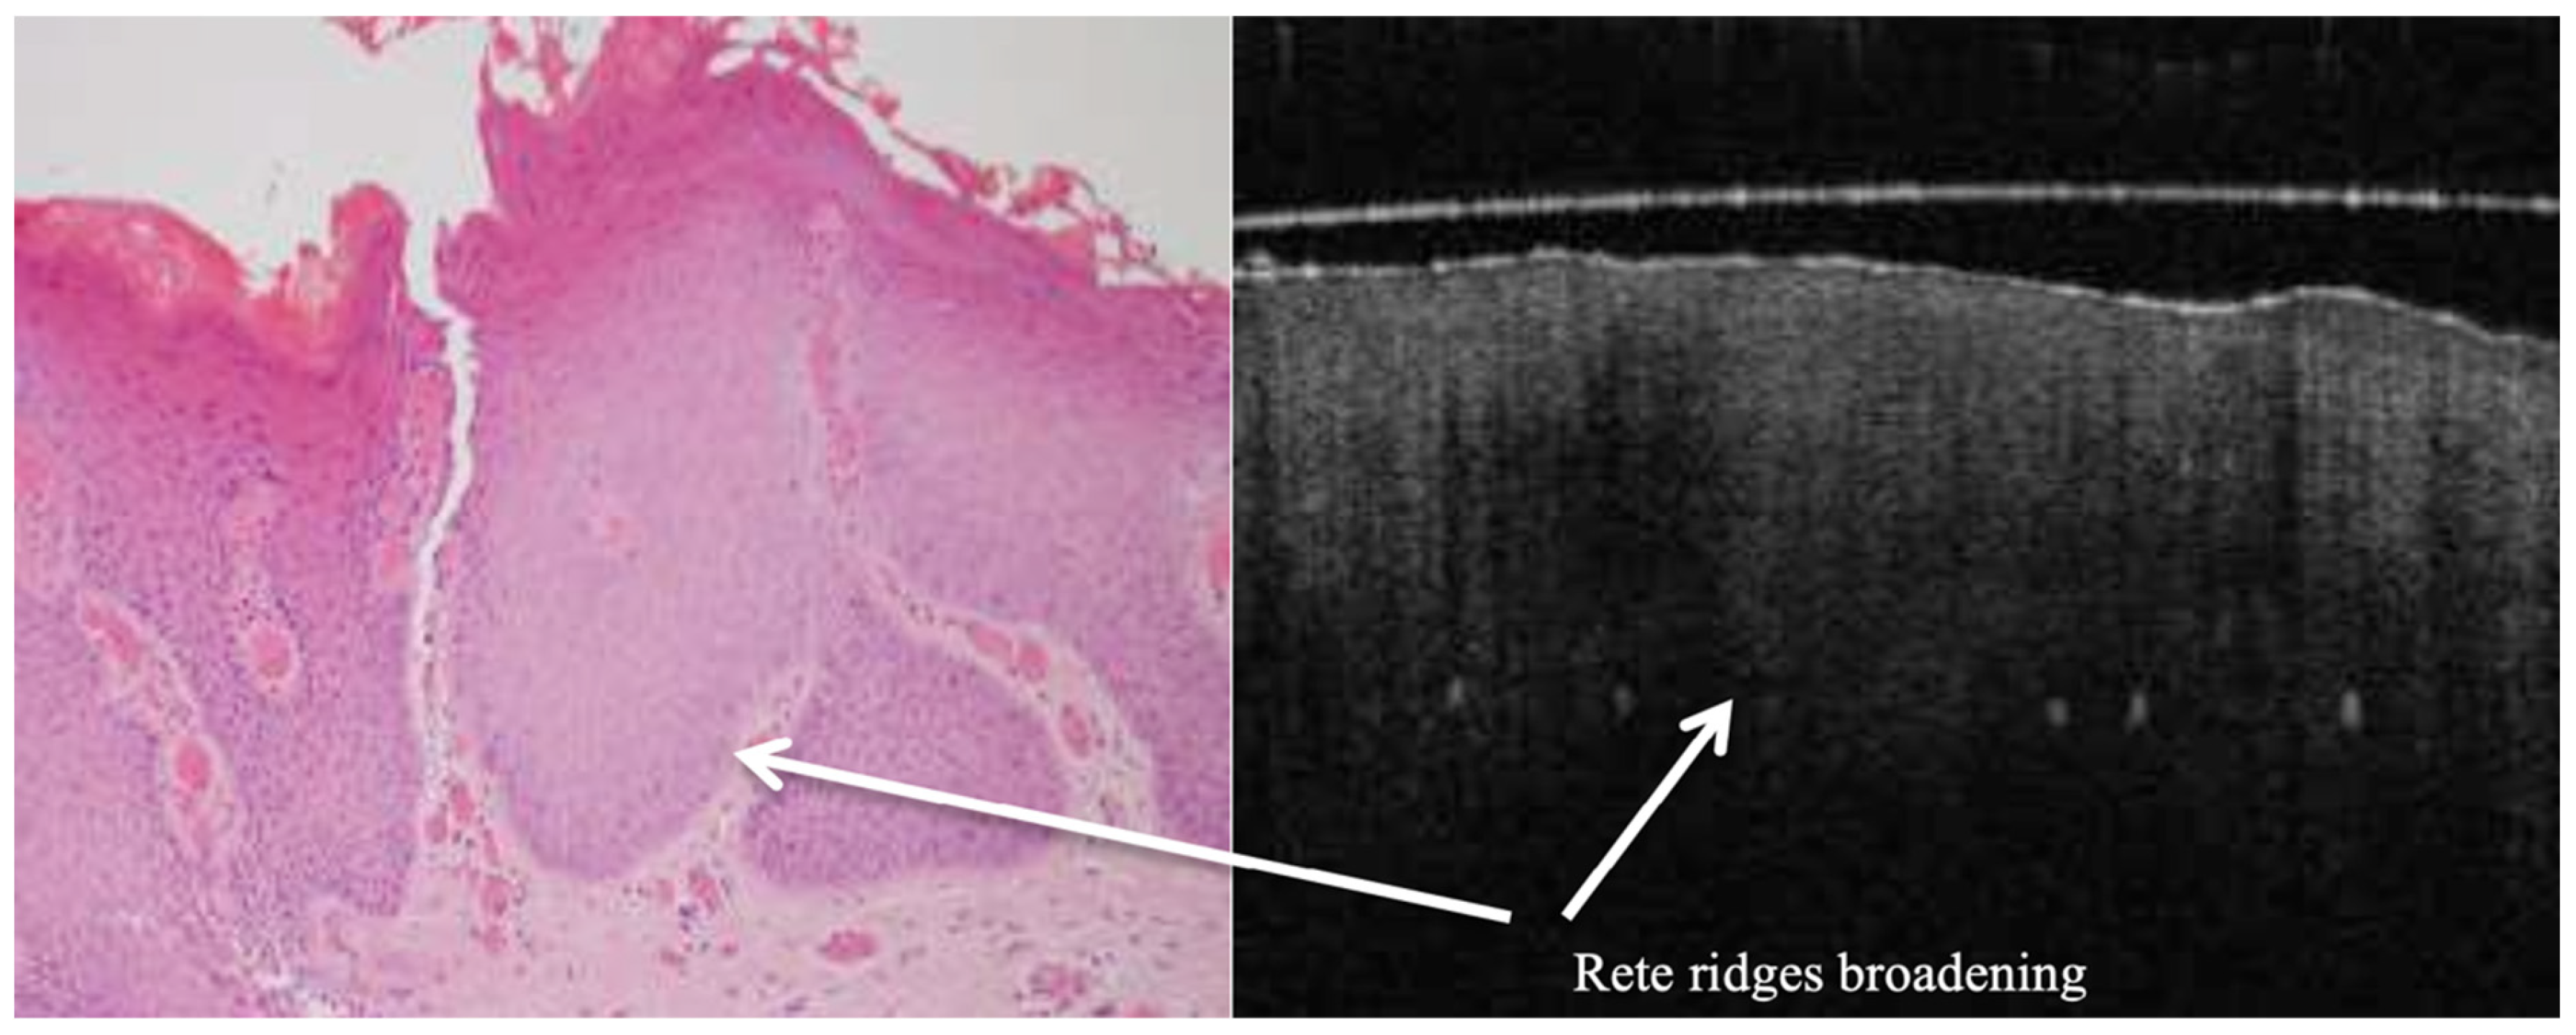

OCT performed well in discriminating dysplasia grades (Figure 1, Figure 2, Figure 3 and Figure 4). The AUC was 0.89 with an 88.0% sensitivity and 90.0% specificity for mild dysplasia. For moderate dysplasia, the highest accuracy was found: 85.0% sensitivity and 92.0% specificity yielded an AUC of 0.91. Severe dysplasia and CIS presented with lower values: the AUCs were 0.87 and 0.86, respectively (Table 4).

Figure 4. In vivo OCT and histopathology images (A,B) of an erythro–leukoplakic lesion of the soft palate revealing multifocal carcinoma (CA). The OCT image matches the histopathology in displaying multifocal epithelial downwards growth and invasion into the subepithelial layers (white arrows). Furthermore, the basement membrane is indiscernible through the entire OCT scan as a coherent prominent landmark. The bottom image (C) is an in vivo OCT image of a transition zone (blue arrow) between the healthy tissue and invasive carcinoma (CA) invading through the basement membrane. It also shows the normal thickness of the stratified squamous epithelium, which is darker compared to the homogeneous lamina propria; while crossing the transition zone, epithelial downgrowth and invasion can be clearly recognised, and the lamina propria becomes non-homogeneous. BM = basement membrane; EP = epithelium; LP = lamina propria; CA = invasive carcinoma.